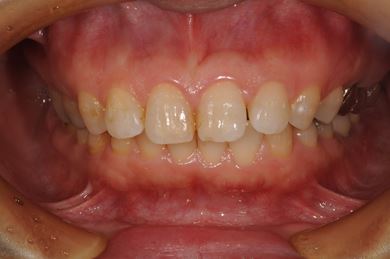

抜歯即日スピードインプラント治療+セラミック治療+歯肉歯槽骨整形術

| 治療内容 | インプラント2本(抜歯即日スピードインプラント)、ハイブリッドセラミッククラウン2本、歯肉歯槽骨整形術 | ||||||||||||||||||||||||||||||||